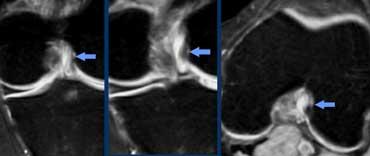

Lưu ý rằng trên ảnh mặt phẳng vành và mặt phẳng ngang, các bó sợi ACL nằm sát ngay bên cạnh xương của hõm liên lồi cầu (mũi tên).

Tuyệt đối không được có dịch giữa các bó sợi ACL và xương lồi cầu ngoài (gọi là ‘dấu hiệu hõm rỗng’).

Đứt PCL cấp tính: Trên mặt phẳng vành và mặt phẳng ngang, hầu hết các bó sợi đã mất, đây là tổn thương độ cao.

Dây chằng chéo sau

Chúng ta áp dụng các tiêu chuẩn tương tự cho tất cả các dây chằng khác trong cơ thể.

Ca bệnh bên trái cho thấy đứt PCL độ cao.